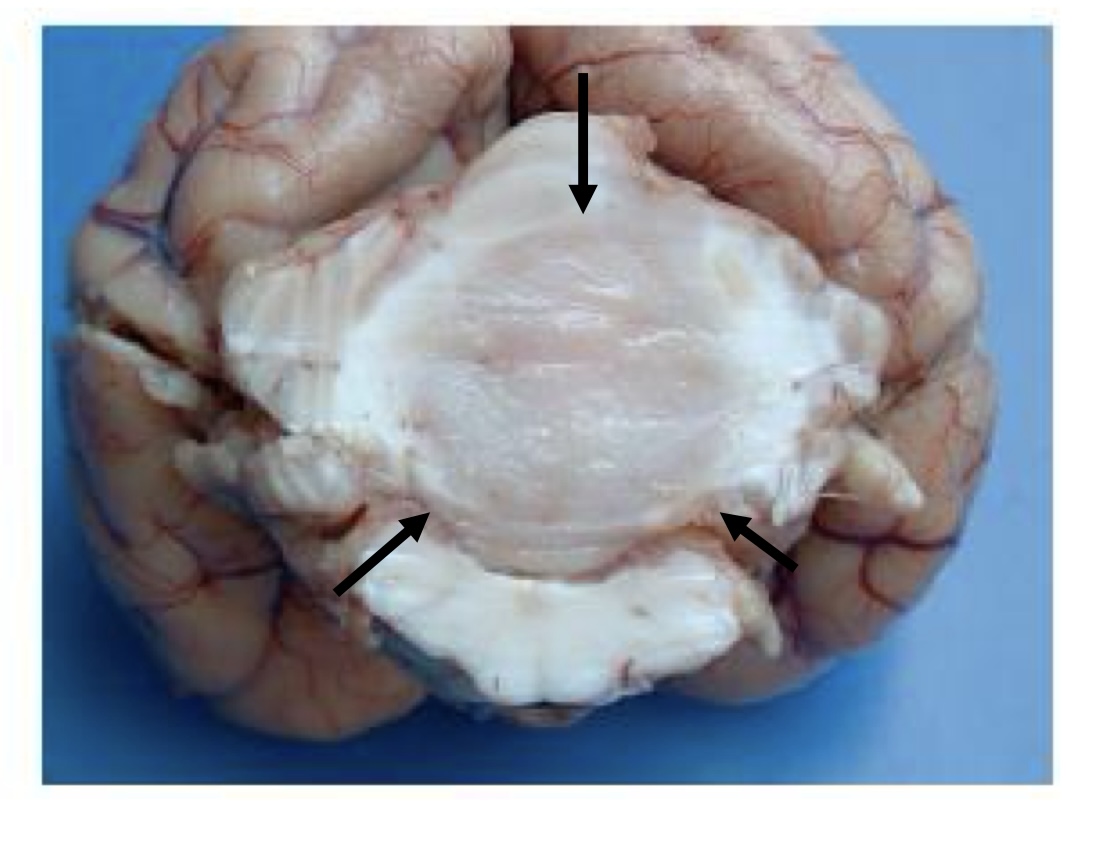

what is this?

medulloblastoma → white to tan, homogenous mass that compresses the cerebellum and brainstem